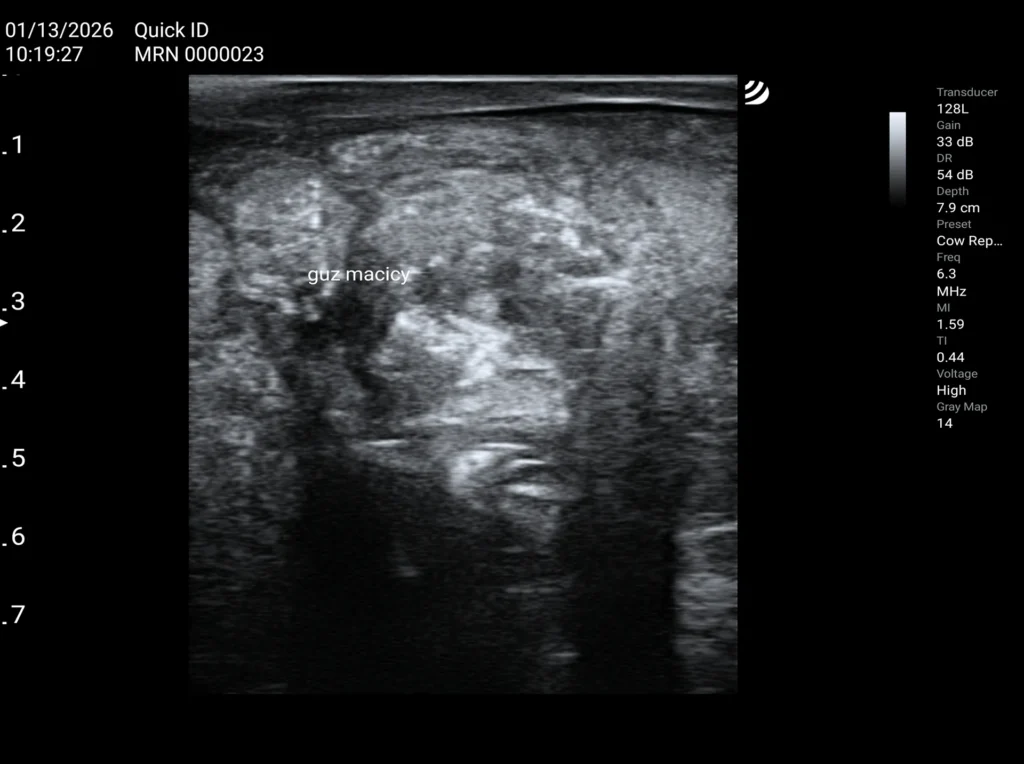

Guzy jajników i macicy u krów

W mojej praktyce najczęściej spotykam się z poporodowymi ropniami ściany macicy.

W przypadkach, gdy guz nie nacieka do światła macicy, odpowiednie przygotowanie do rui oraz inseminacja często kończą się powodzeniem. Należy jednak pamiętać, że rozciąganie macicy spowodowane rosnącym płodem może doprowadzić do pęknięcia ropnia, uszkodzenia ściany macicy, krwotoku lub rozwoju stanów zapalnych.

Sytuacja jest znacznie gorsza, gdy guz penetruje do światła macicy. W takich przypadkach, bez intensywnej antybiotykoterapii (często łączonej – ogólnej i miejscowej) oraz hormonoterapii, skuteczność inseminacji jest znikoma.

W diagnostyce oraz ocenie rokowania pomocne może być badanie dopplerowskie. Obecność przepływów krwi w obrębie zmiany zwiększa prawdopodobieństwo skuteczności antybiotykoterapii ogólnej, ponieważ lek ma możliwość dotarcia do ogniska chorobowego.